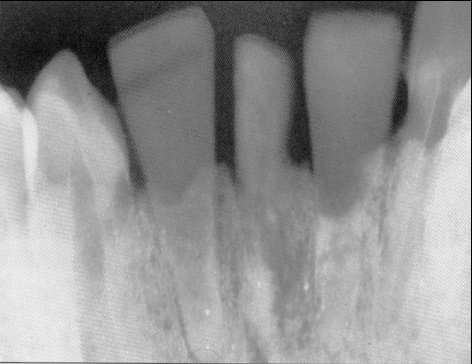

In einem archäologischen Grab auf der Playa de Los Muertos im Ulloa Valley von Honduras wurde 1931 das erste bekannte dentale Implantat der Medizingeschichte entdeckt. In einem großen Unterkieferfragment einer etwa 20jährigen Maya-Frau aus dem 7. nachchristlichen Jahrhundert sind drei verlorengegangene Schneidezähne durch künstliche Zähne aus der Schale einer doppelwandigen Molluske ersetzt. Ursprünglich wurde angenommen, dass dieses Schalensubstitut post mortem inseriert worden ist. Der brasilianische Zahnmediziner Amadeo Bobio konnte 1972 aufgrund radiografischer Untersuchungen nachweisen, dass diese Implantate osseointegriert waren und zu Lebzeiten eingesetzt worden sind.(Zitat:Dr.Dr.Sprang)